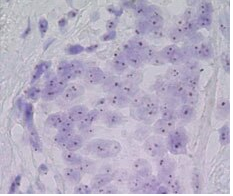

CISH

或称原位显色杂交,

是一种用标记的互补DNA或RNA链在组织标本中定位特定DNA或RNA序列的过程。CISH方法学可用于评价基因扩增、基因缺失、染色体易位和染色体数目。CISH利用常规过氧化物酶或碱性磷酸酶反应,在标准的白光显微镜下观察,适用于福尔马林固定、石蜡包埋(FFPE)组织、血液或骨髓涂片、中期染色体扩散和固定细胞。

技术资料图片1

CISH 特点:

• 观察组织形态同时评估基因状态

• 使用明场显微镜和处理方法类似免疫组化

• 定量结果